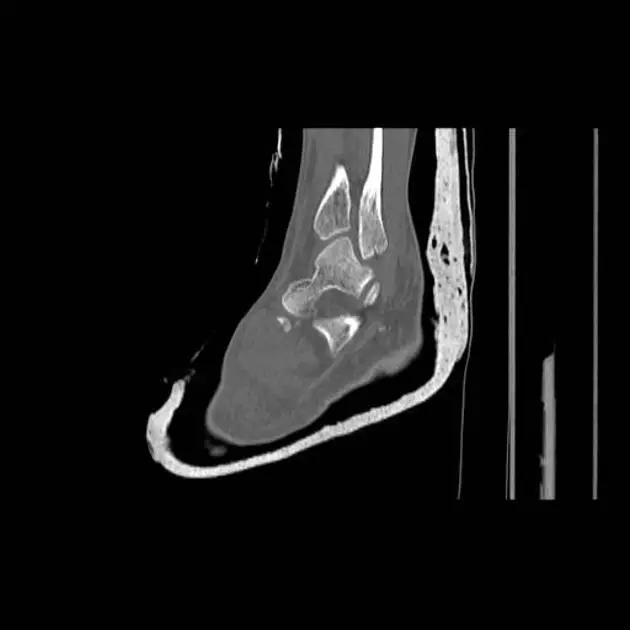

1. 三平面骨折(Triplane fracture )

即累及远端胫骨骨骺的骨折可因骨折线延入其他两个平面而变得复杂,因而称之。骨折由矢状面内的骨骺骨折,经生长板外侧面的轴位面内水平方向骨折,与冠状面内经干骺端到骨干的斜行骨折,自生长板的前侧面伸延至胫骨的后侧皮质。

三平面骨折 CT 片

三平面骨折 CT 重建